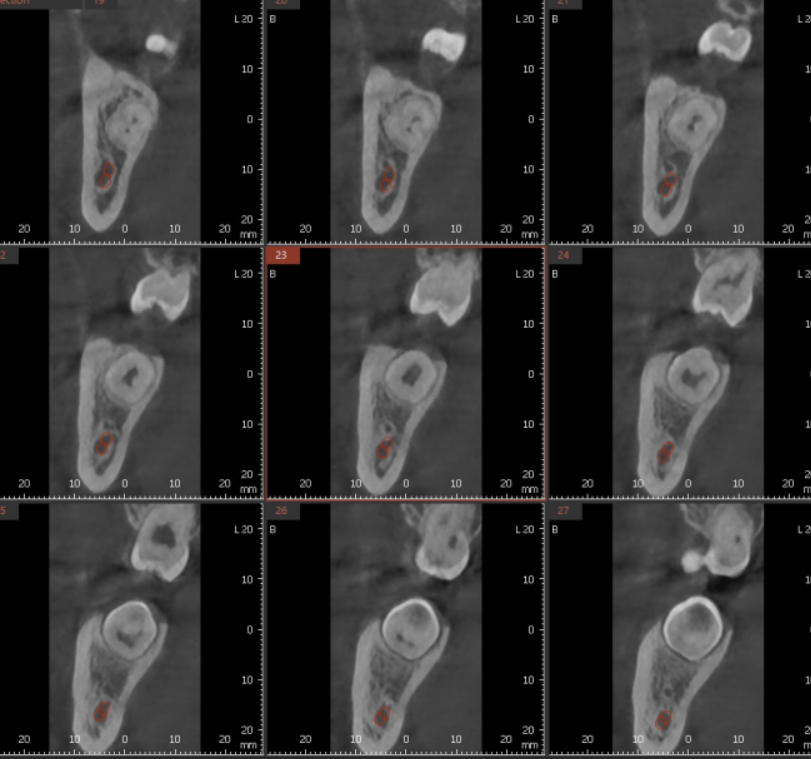

해부학적으로 하치조 신경관과 근접하기 때문에

뽑고 나서 신경 손상 가능성도 있고요

그래서 꼭 ct를 찍어

안전한 상일동 사랑니 발치를 추구합니다.